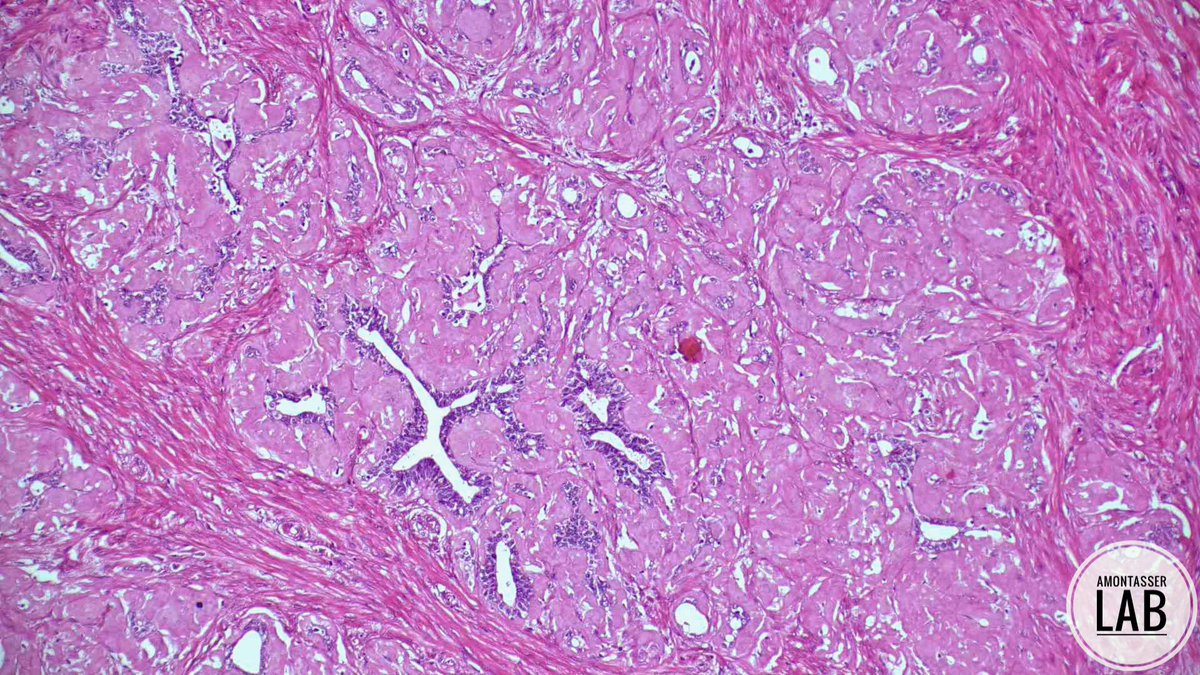

Seminal vesicle amyloidosis: ✅ A finding in up to 10% of RPs. ✅ Mimics T3b disease intra-operatively. ✅ Usually represents a localized form rather than part of a systemic process. ✅ Suepithelial deposition of amorphous hyaline material, Congo Red + #PathTwitter #GUpath

1

14

58